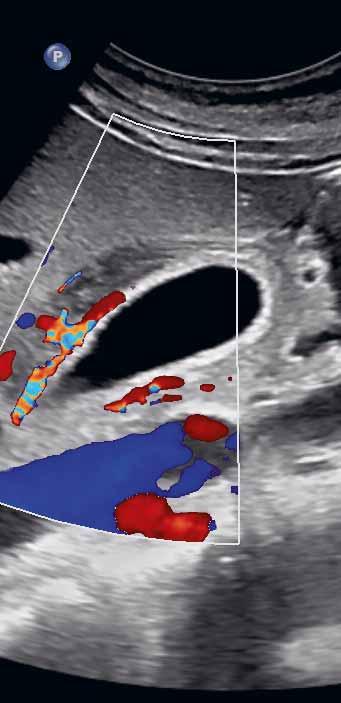

Postprandiálně se mírně dilatuje ductus hepatocholedochus. Potrava přítomná v duodenu ztěžuje zobrazení distálního a intrapankreatického hepatocholedochu. Artefakty z duodena, které naléhá na spodní stěnu žlučníku, mohou imitovat patologii stěny žlučníku či drobnou vícečetnou cholecystolitiázu. Za duodenem však nevzniká typický dorzální akustický stín jako za konkrementy, ale reverberační artefakty v podobě hypoechogenního akustického „šumu“ (obr. 1.2).

Obr. 1.2 Imprese duodena do kaudální stěny žlučníku